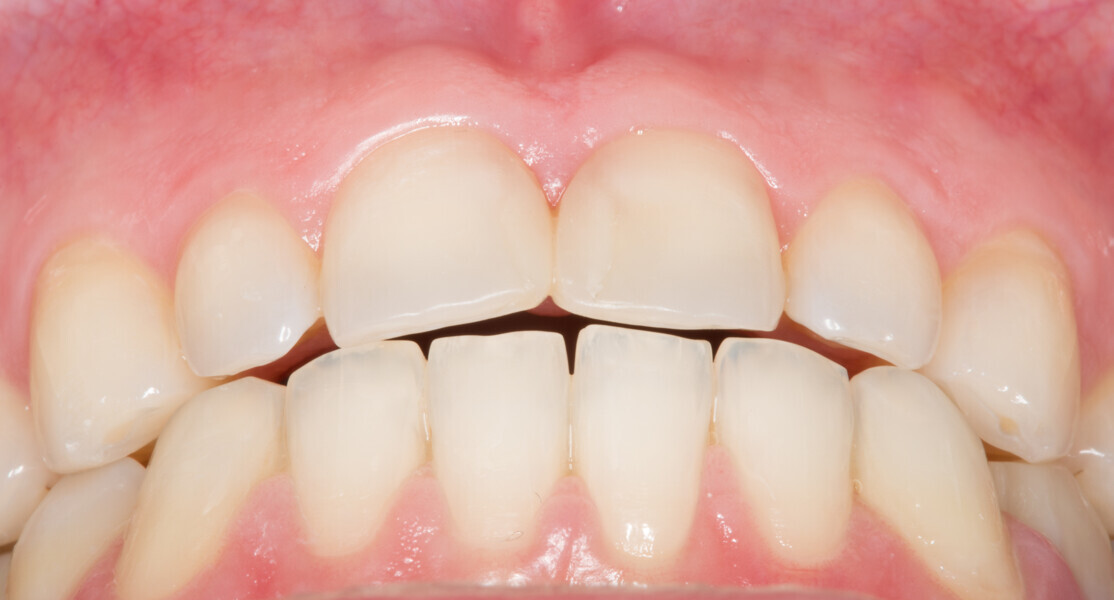

Fig. 2: Initial clinical situation.